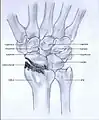

Stage III

Stage IV

- Stage III: the osteoarthritis is localized in the entire radioscaphoid joint with involvement of the capitolunate joint.

- Stage IV: the osteoarthritis is located in the entire radiocarpal joint and in the intercarpal joints. It also may involve the distal radio-ulnar joint (DRUJ).